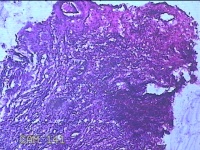

左侧卵巢囊肿⑴

性别

女

年龄

34岁

临床诊断

左侧卵巢子宫内膜异位囊肿

一般病史

下腹痛3小时入院。

标本名称

大体所见

灰白暗红色囊性肿物8x2.5x0.7cm一个,表面糜烂,部分已切开,囊内容物已流失,囊壁厚0.1cm。

图2